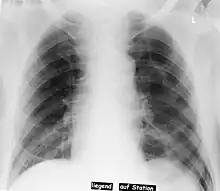

Deep sulcus sign

Pneumothorax left sided

In radiology, the deep sulcus sign on a supine chest radiograph is an indirect indicator of a pneumothorax.[1][2] In a supine film, it appears as a deep, lucent, ipsilateral costophrenic angle[3] within the nondependent portions of the pleural space as opposed to the apex (of the lung) when the patient is upright. The costophrenic angle is abnormally deepened when the pleural air collects laterally, producing the deep sulcus sign.[4]